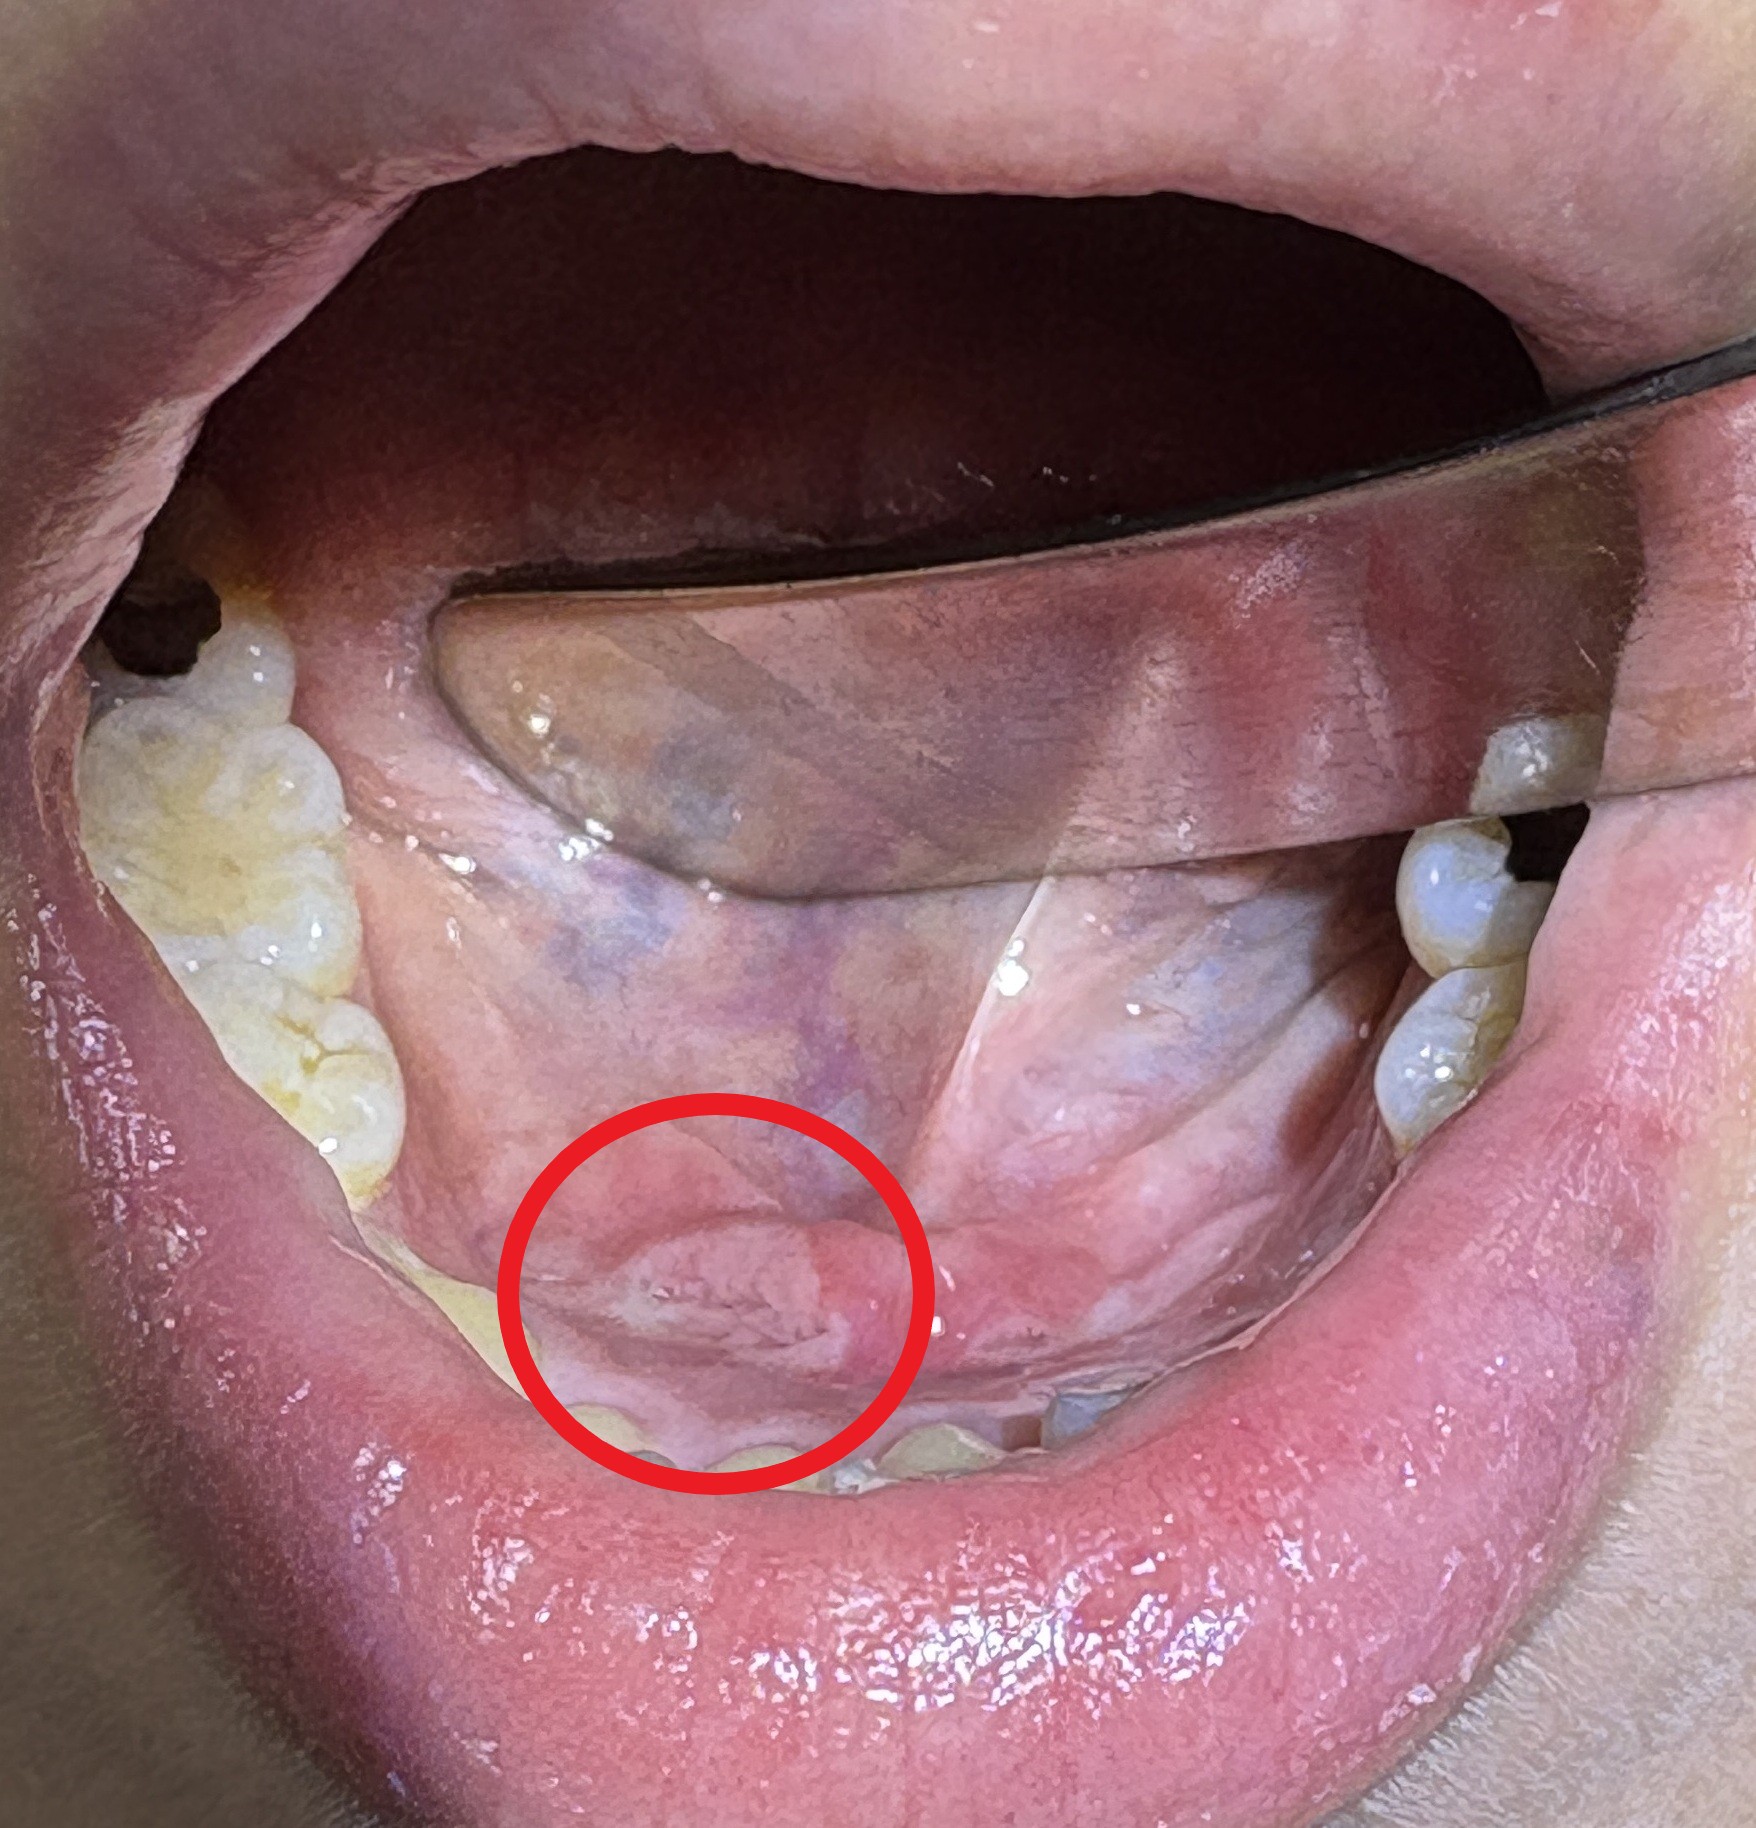

続いて喉👄をチェックします。

ぱっと見 口の中も問題無さそうですが、こういった場合は関連痛を考慮し、舌の裏側や舌の付け根 など 隅々まで

チェックします。

原因が判明しました![]()

どれかと言いますと↓

舌の裏面(医学的には口腔底)に口内炎が出来ていました。 これが痛みの原因です。